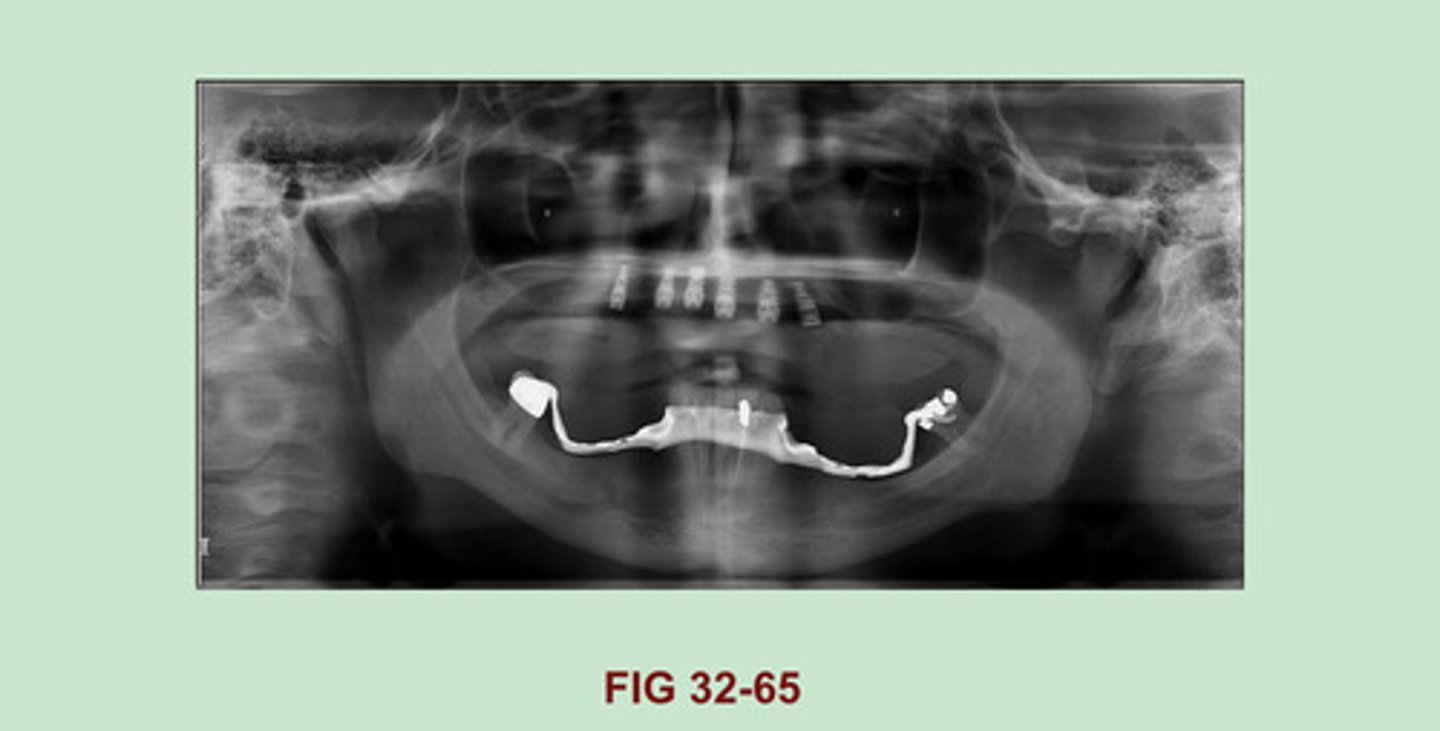

IDENTIFY the dental materials seen in the MAXILLA; IDENTIFY the RADIOPAQUE FRAMEWORK MATERIAL seen on the MANDIBLE on this panoramic image. (Figure 32-65).

Maxilla: Dental implants

Mandible: Partial denture or special appliance space holder (correct me if I am wrong, this one I did not see in the textbook).